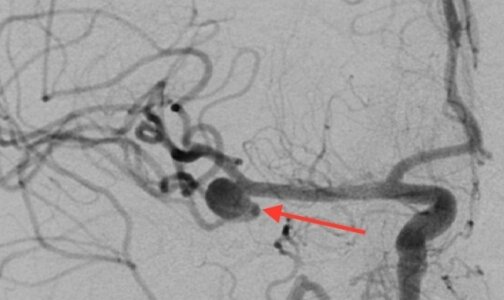

- Мы приняли решение начать с церебральной ангиографии - выявили аневризму средней мозговой артерии и выполнили ее эмболизацию, устранили источник кровотечения, - рассказал Сергей Шендеров. - И тут же приступили к коронарной ангиографии со стентированием коронарных артерий, поскольку после эмболизации уже можем ввести антикоагулянты. На ангиографии было обнаружено поражение передней межжелудочковой артерии, в которой и выявился на кардиограмме подъем сегмента ST. В эту зону имплантировали стент.